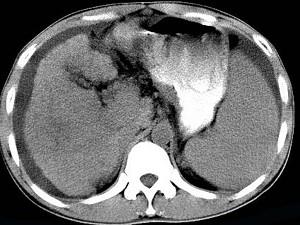

问题 男,35岁,有乙肝病史多年,AFP阳性,影像检查如图,最可能的诊断是 ( )

选项 A、肝癌、硬化腹水 B、肝硬化、结节性增生 C、肝血管 D、肝脓肿 E、肝硬化腹水

答案 A